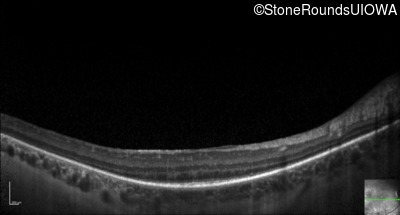

Optical Coherence Tomography - Left - 20/32 -1

Exemplar / OCT Stack

OCT Stack